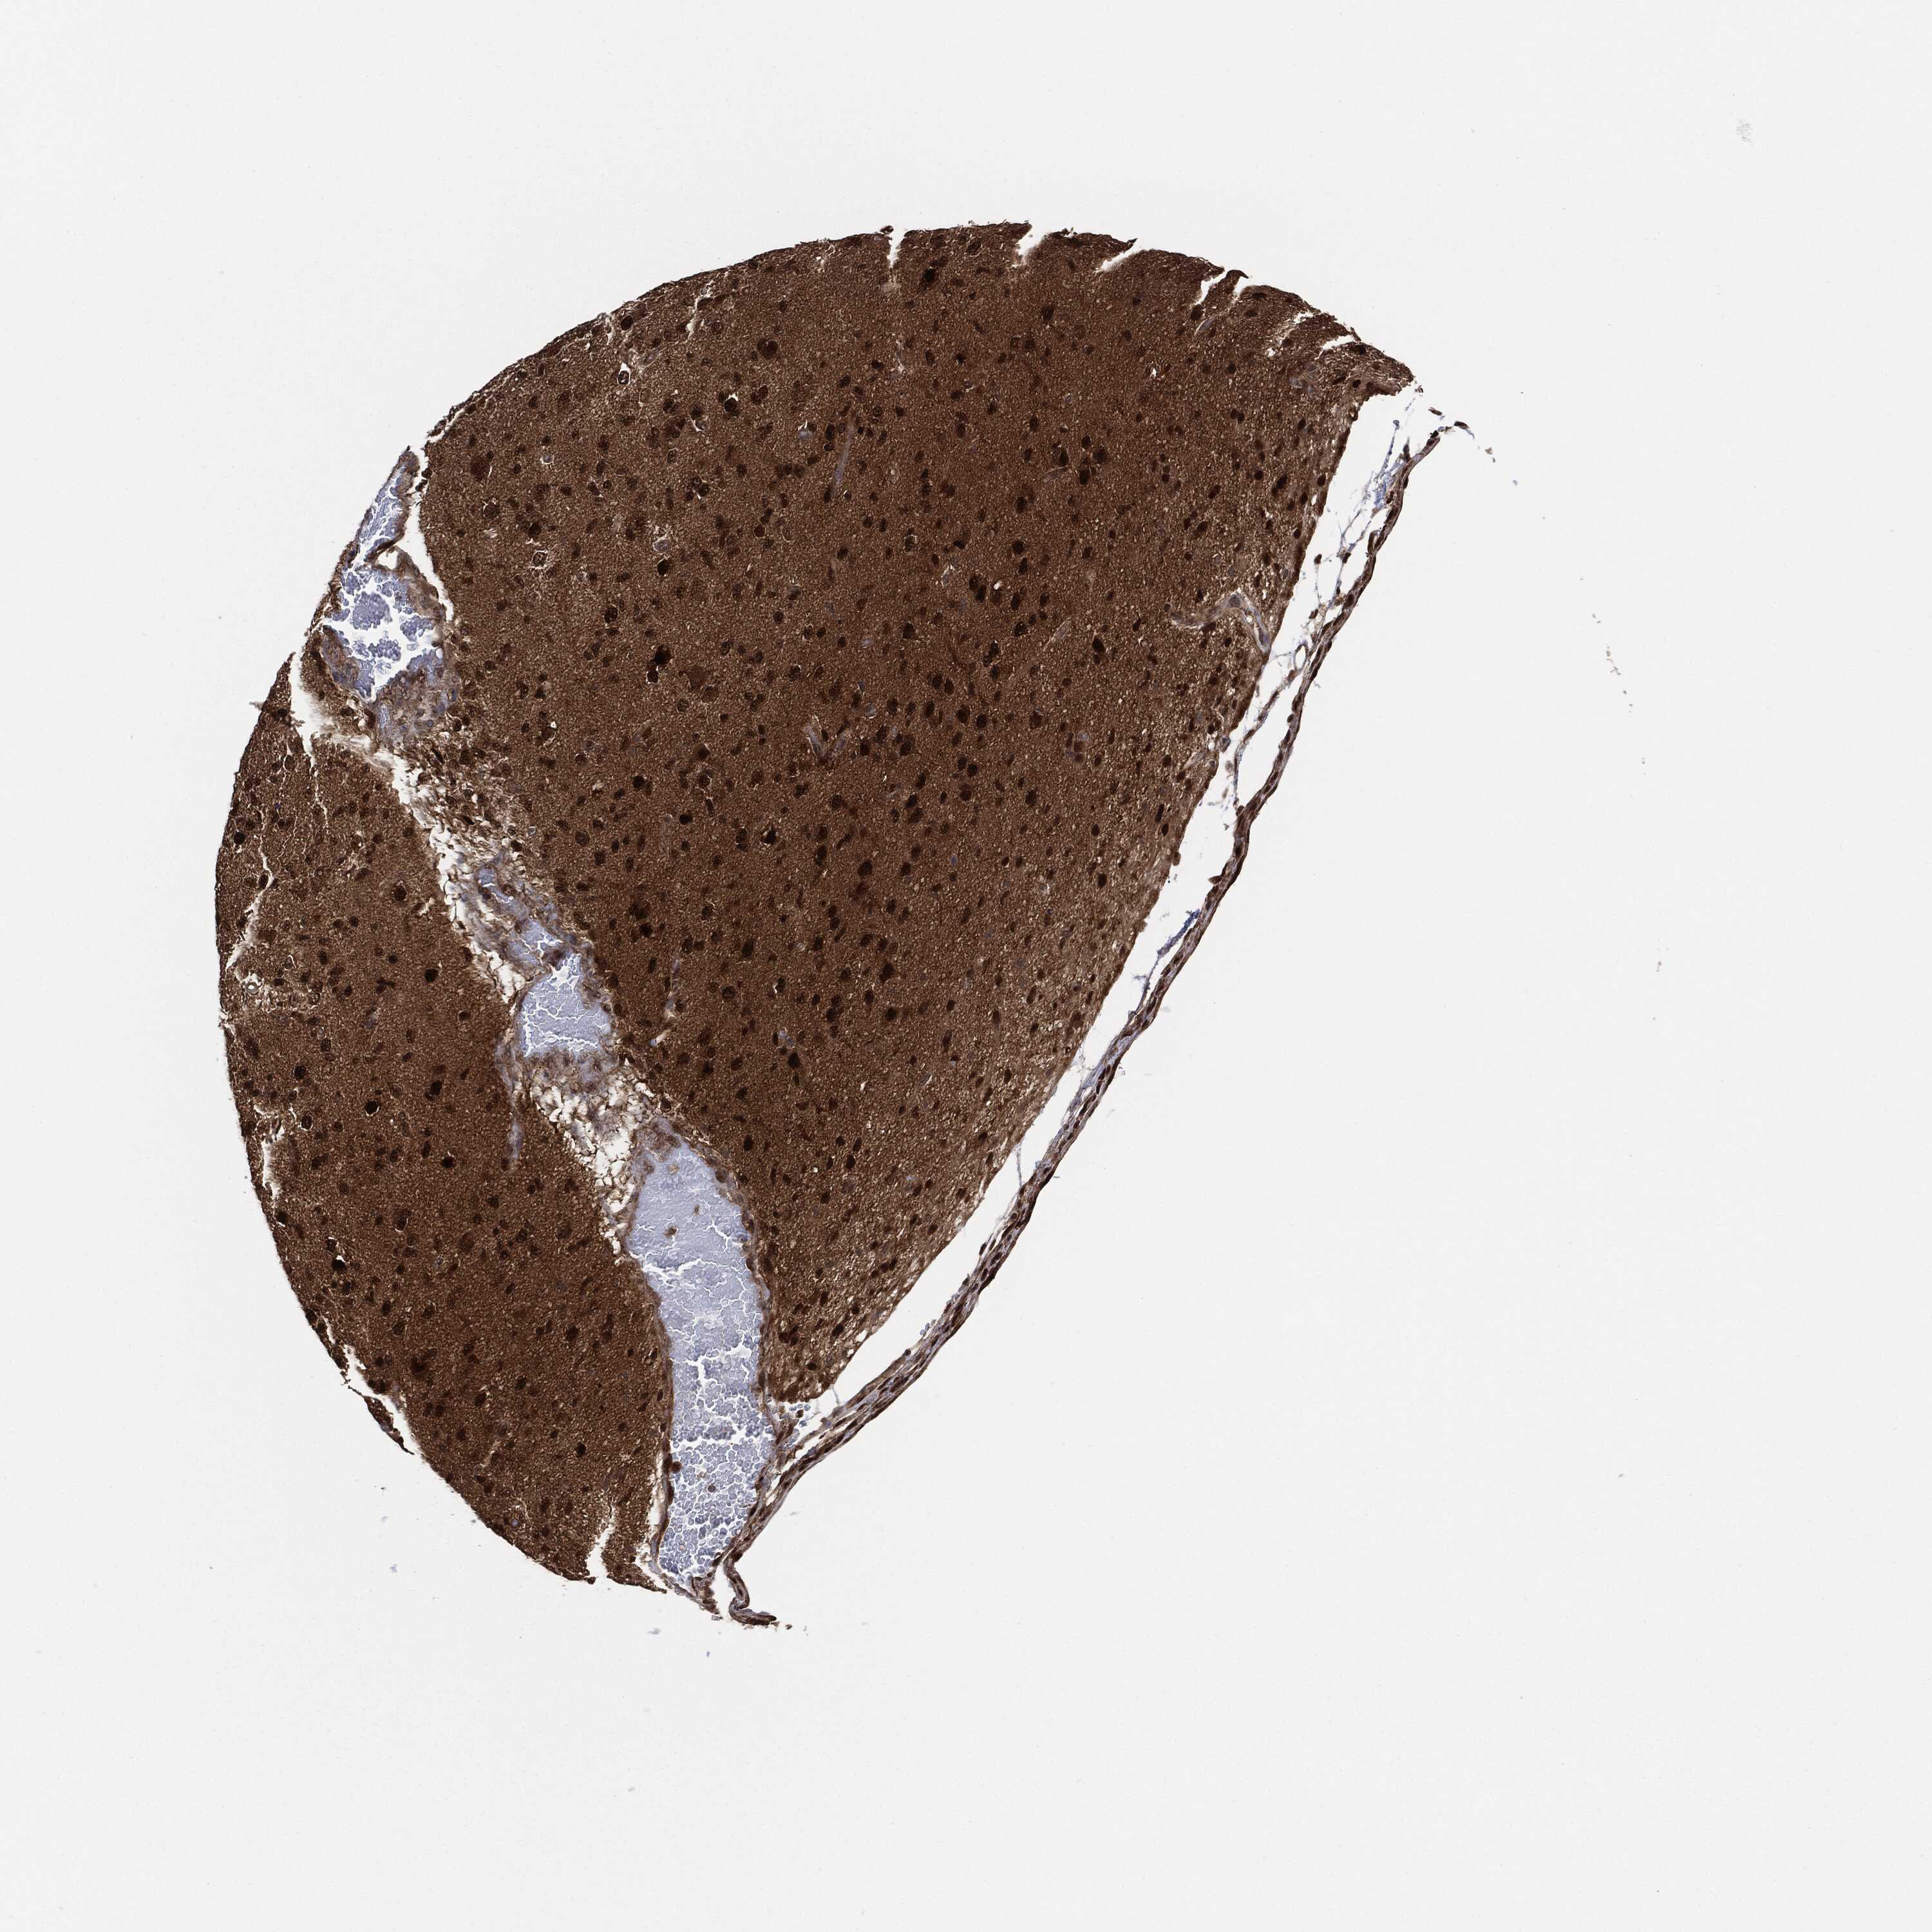

GLIOMA - Protein expressioni

A mouse-over function shows sample information and annotation data. Click on an image to view it in a full screen mode. Samples can be filtered based on level of antibody staining by selecting one or several of the following categories: high, medium, low and not detected. The assay and annotation is described here.

Note that samples used for immunohistochemistry by the Human Protein Atlas do not correspond to samples in the TCGA dataset.

Antibody stainingi

Antibody staining in the annotated cell types in the current human tissue is reported as not detected, low, medium, or high, based on conventional immunohistochemistry profiling in selected tissues. This score is based on the combination of the staining intensity and fraction of stained cells.

Each image is clickable and will lead to virtual microscopy that enables deeper exploration of all samples and also displays staining intensity scores, fraction scores and subcellular localization as well as patient and tissue information for each sample.

Antibody HPA034635

Antibody HPA069977

Antibody HPA071875

Antibody CAB009108

Staining

High

Medium

Low

Not detected

Intensity

Strong

Moderate

Weak

Negative

Quantity

>75%

75%-25%

<25%

None

Location

Nuclear

Cytoplasmic/membranous

Cytoplasmic/membranous,nuclear

Glioma, malignant, Low grade

Glioma, malignant, High grade